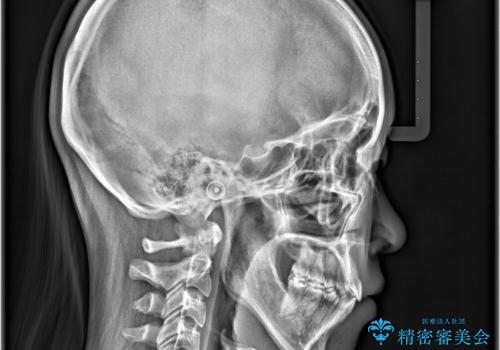

- 八重歯と口元が出ていることを主訴に来院されました。

レントゲンの検査において、前歯も外側に傾いてる結果であったため、上下左右の小臼歯を抜歯して配列を行いました。

歯の動きも良く短期間で治療を終えられたため患者さんにも大変満足していただきました。